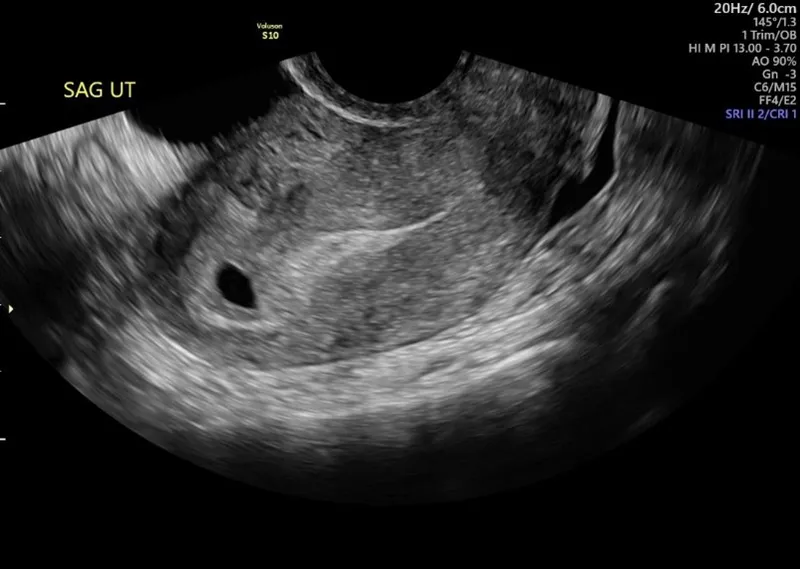

- Confirms Intrauterine Pregnancy (IUP), viability, and dates early gestation.

- Transvaginal Sonography (TVS) preferred over Transabdominal (TAS) for superior resolution.

- Gestational Sac (GS): 4.5-5 wks. First reliable sign of IUP.

- Yolk Sac (YS): 5-5.5 wks. Confirms IUP definitively.

⭐ The Double Decidual Sac Sign (DDSS) on TVS is an early reliable indicator of IUP, seen around 4.5-5 weeks, before the yolk sac visualization is definitive for IUP confirmation prior to embryo visualization.

- 1st Trimester:

- Double bleb sign: IUP (yolk & amniotic sacs).

- Double decidual sign: Confirms IUP.

- Earliest TVS signs: GS (4.5-5w), YS (5-5.5w), Fetal Heart (5.5-6w).